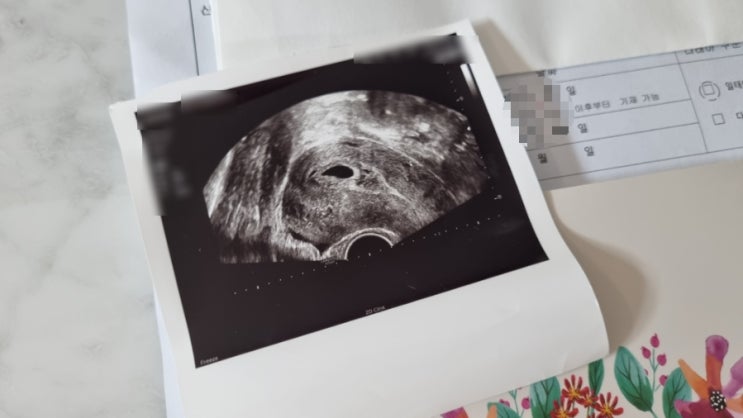

초저출산시대를 역행하는 삶, 용띠맘 임신 소식 = 임신 초기 챙겨야하는 것들 (입덧약 보험청구, 산후조리원 예약, 정부 및 지자체 지원 등등)

유산 소식을 전한 지 얼마 되지 않은 것 같은데 감사하게도 금방 다시 임신이 돼서 내년 용띠맘을 준비하고...